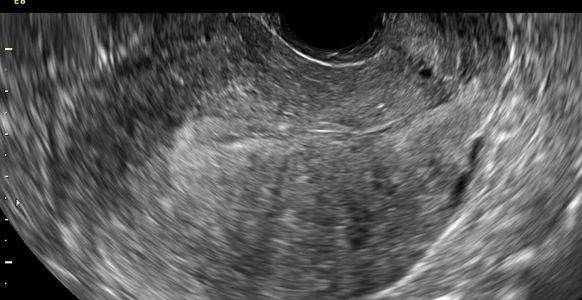

The chance of miscarriage decreases dramatically after 9 weeks if the embryo is normal in size with a normal heart beat by ultrasound. If a heartbeat is present between 6 and 9 weeks, then there is still a chance of early miscarriage. Ultrasound findings of a nonviable pregnancy vary with the stage of pregnancy that was achieved. These include

Other abnormal findings include irregular shape of the gestational sac, abnormal position (within the uterine cavity or low, indicating a miscarriage in progress), poor surrounding choriodecidual reaction, and abnormal internal morphology including an 'empty amnion'.